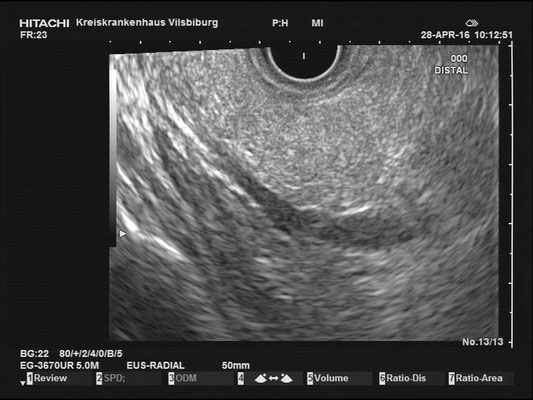

Normal findings - Pancreas / Common bile duct (CBD)

Pancreas

The images above depict a thorough inspection of the pancreas, as seen in an radial EUS Examination. We begin (hopefully ;) bei identifying the uncinate process between the golden V, which is formed by the aorta/V. cava and the mesenteric vessels. After spotting die usually hypoechoic ventral pancreatic root, the duodenal papilla can be identified (for a more detailed approach, please visit "Learning Endosono"). By following the splenic vein, the body and tail of the pancreas can be examined.

The most observant viewers will have noticed that not all images above depict normal findings but some abnormalities. (my bad ;)